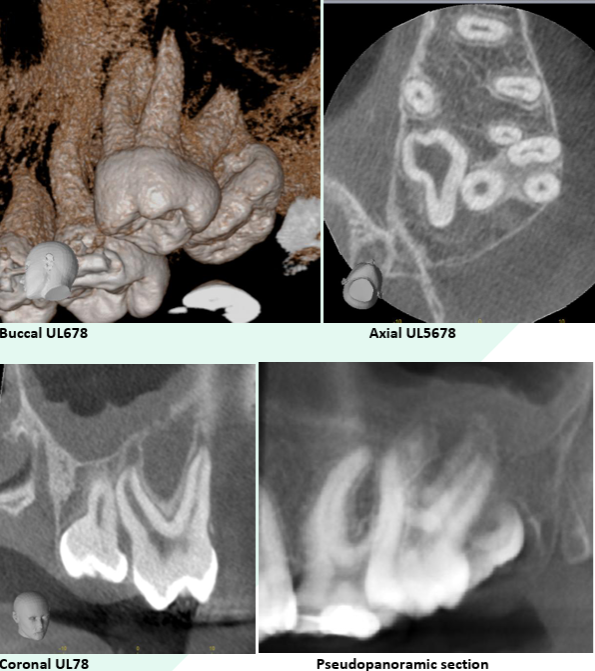

– Precise measurements and high-resolution annotated screenshots

Evaluating for implants

Bone measurements for implant planning

Sinus evaluation